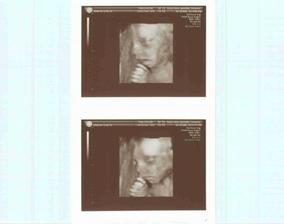

Jsme spolu 15 let,8 let už žijeme ve stejné domáctnosti a letos v červnu 28. jsme se vzali a po svatebních radovánkách přesně 30.06. jsem otěhotněla a tak teď už jsem ve 4.měsíci a čekáme co to bude a těšíme se až budeme tři...lépe řečeno až nás bude o jednoho více...máme 3pejsky,kočku a papouška...takže už je nás v domáctnosti habaděj...Tak čekáme chlapečka,bude se jmenovat Richard...a už jen 3 týdny a snad bude bez komplikací mezi námi...za celé těhotenství jsme neměli žádné problémy tak uvidíme jak proběhne porod a to ostatní...